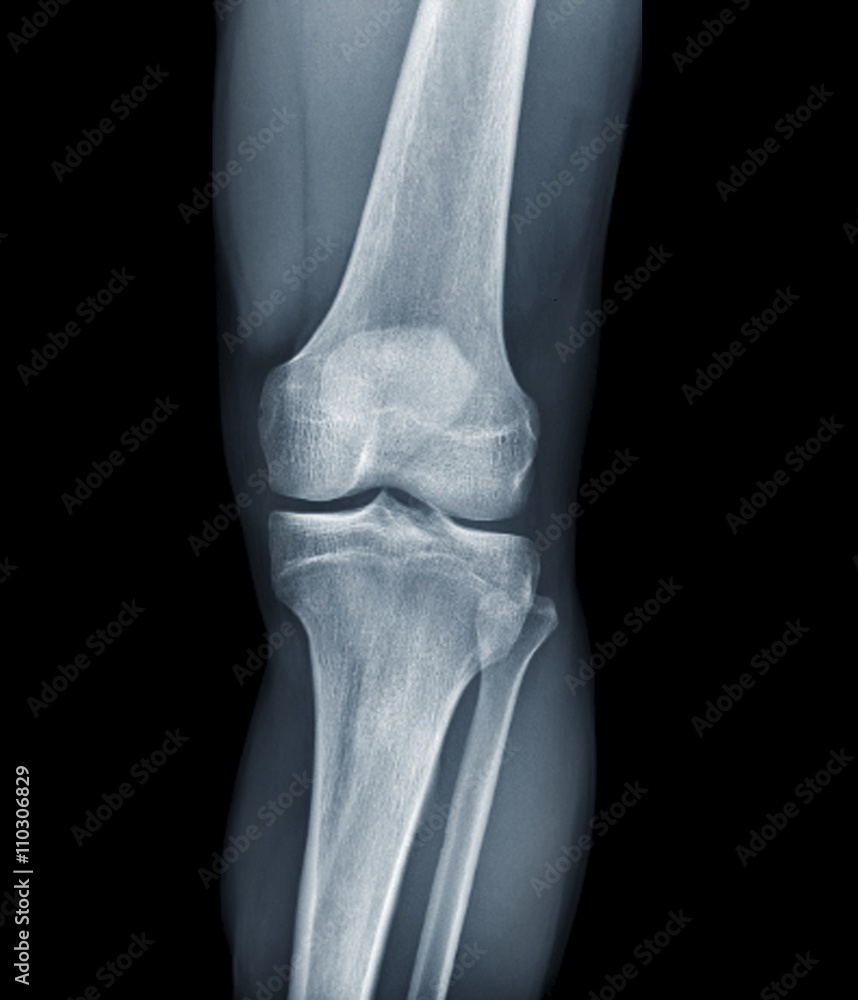

Normal appearances of the knee joint in the growing patient. Citation, doi, disclosures and article data. There mild or borderline patella alta. Education and training, education, plain radiographic studies, paediatric, musculoskeletal joint.

Normal Knee X Ray 13 Year Old - Normal appearances of the knee joint in the growing patient. Web this is a repository of normal pediatric bone xrays and their examples for a quick reference look. It can show broken bones or a dislocated joint. Web normal ap and lateral knee radiographs in an adult male for reference. This article lists examples of normal imaging of the pediatric.

Normal Knee X Ray 13 Year Old - Normal appearances of the knee joint in the growing patient. There mild or borderline patella alta. Web normal ap and lateral knee radiographs in an adult male for reference. Citation, doi, disclosures and article data. Web this is a repository of normal pediatric bone xrays and their examples for a quick reference look.